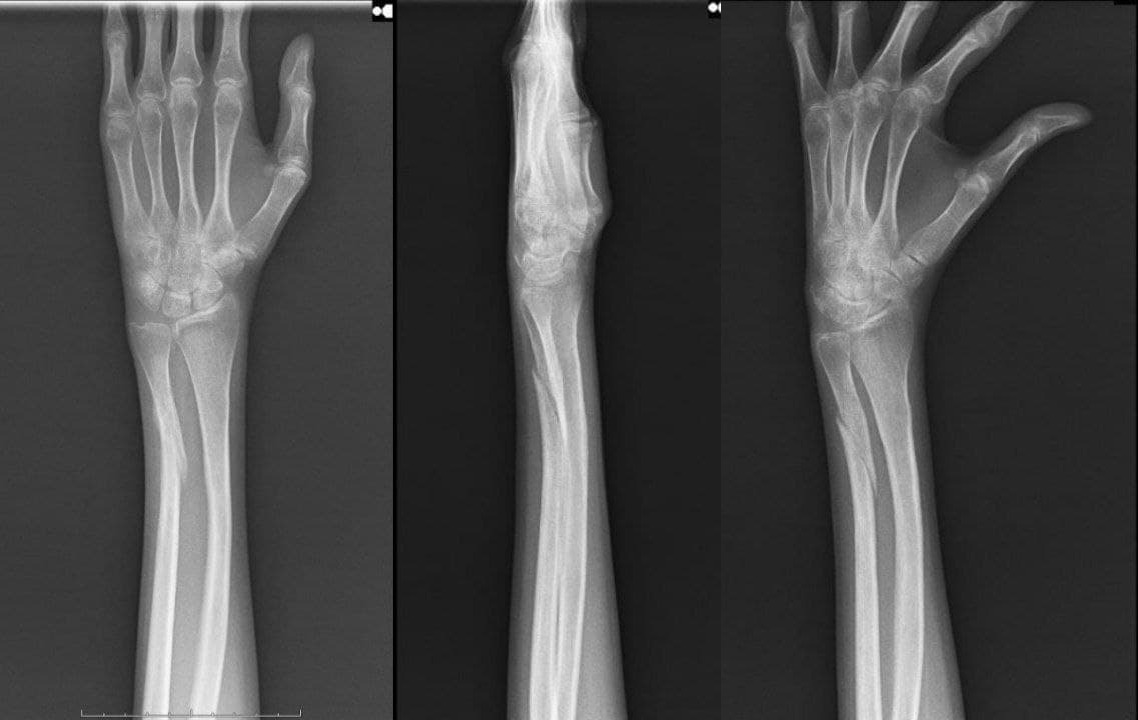

Рентгеновский снимок предплечья в гипсе в день первой встречи - виден перелом локтевой кости.

Рентген контроль сращения через 8 недель - видны признаки замедленной консолидации, допустимое угловое смещение отломков.

Рентген контроль сращения через 12 недель - признаки консолидирующегося перелома локтевой кости.